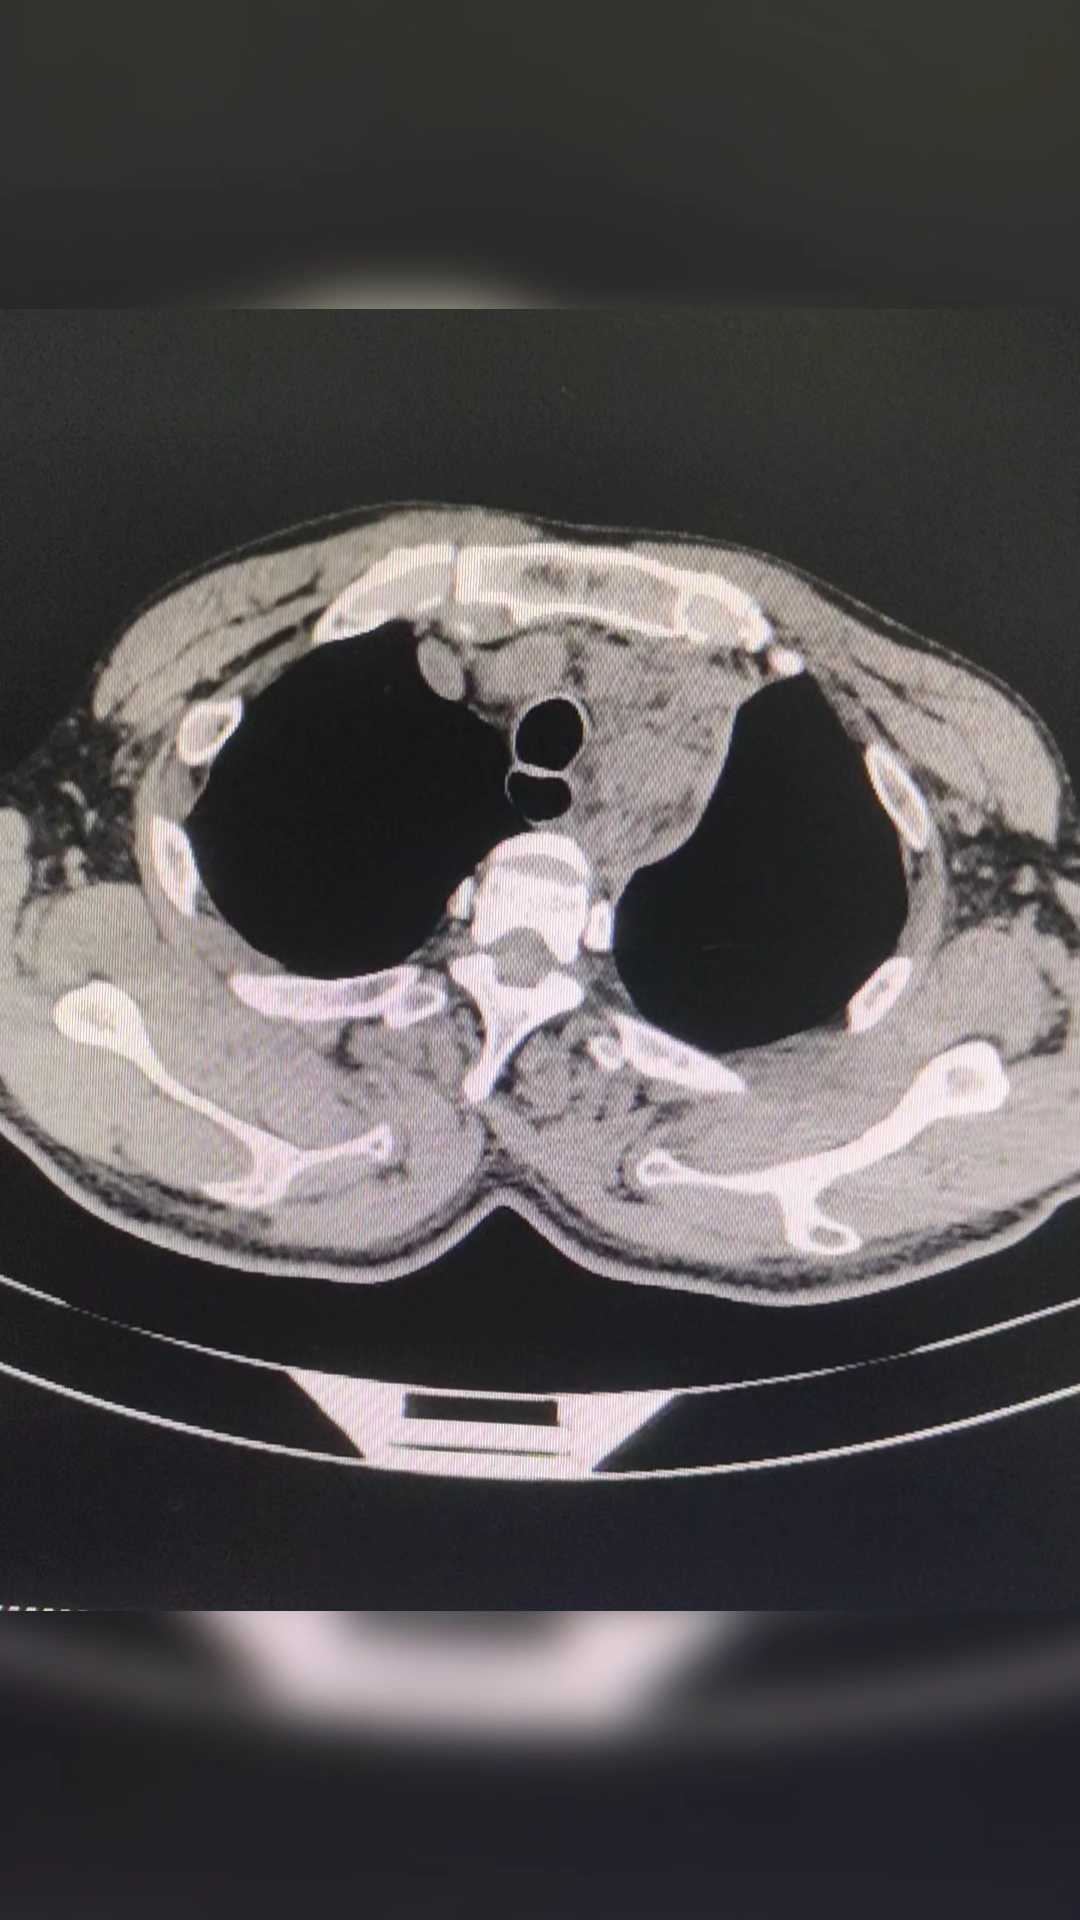

看过CT,园友们能看出是什么病吗?

主动脉夹层!

这个结果,是不是有点意外?因为症状不典型,如果不查CT,只按心脏的问题处理,那就麻烦大了!

急性 主动脉夹层 最典型症状为突发性剧烈胸/背疼痛,通常会伴有低血压和休克,其他特征性临床表现为心包积液、主动脉瓣反流和冠状动脉受累等。但是这个患者的胸痛不是很重,也没有低血压,双上肢的血压也没有明显的差距!特征性的表现,也就是心包积液了!